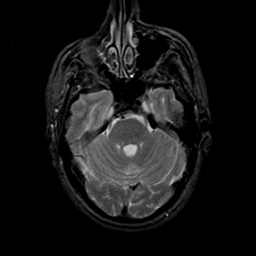

MR Study #23, January 26, 1992 -- Slice #14